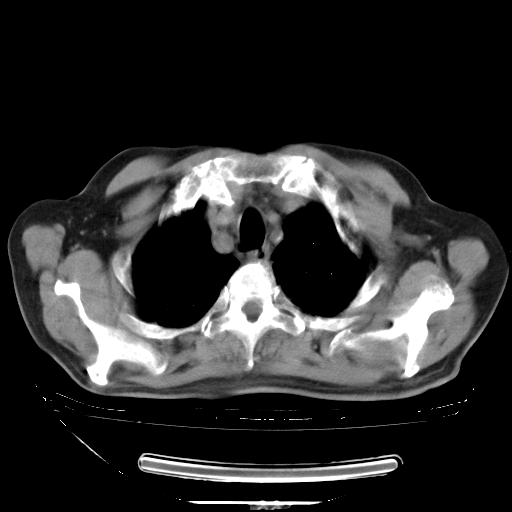

5月9日肺部CT(在4月27日齐鲁医院肺部CT描述部分肺组织磨玻璃样改变,12天后肺组织广泛磨玻璃样改变)

2009年5月9日肺部CT

大致读了系列胸部CT:纵隔窗无明显异常,肺窗:从4、27至今:主要是双肺中下野外带可见毛玻璃样改变,目前处于急性肺泡炎阶段,至于原因考虑1、结替组织或胶原血管性疾病所致?2、恶性疾病如恶组在肺部所致的表现或细支气管肺泡癌?3、药物或其它原因如肺蛋白沉着症所致肺泡炎目前不太可能?总之,明天就去请我院的呼吸科、感染科、血液科和临免专家会诊哈。